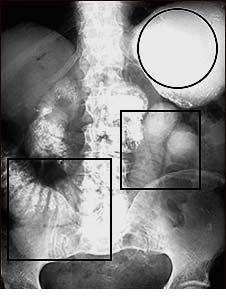

Ocluzia intestinala sau blocarea intestinului